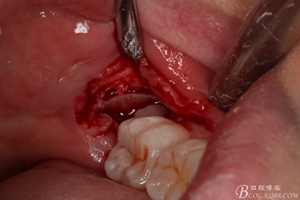

圖9.翻開瓣,可見38部分牙冠暴露

圖10. 翻開瓣。38牙冠還有部分骨質(zhì)覆蓋,遂用高速牙鉆去骨

圖11.去骨---暴露出38的牙冠最大周徑